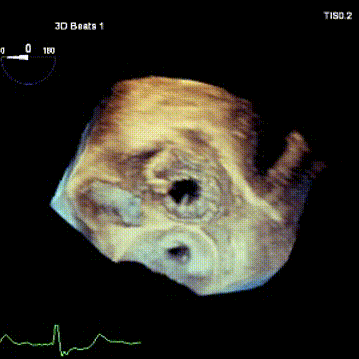

手术在患者全麻状态下进行,采用经右侧颈静脉作为入路,将装载有人工瓣膜的输送器缓慢推送至右心房;并在经食道超声和DSA的引导下小心调整输送器角度,将输送器送入右心室;逐步释放瓣膜锚定装置和盘片,调整瓣膜位置后,锚定瓣膜完成植入。术后右房压明显下降,从术前的25/10(16) mmHg降至术后即刻的12/7(10) mmHg,术后超声提示人工三尖瓣同轴性良好,固定牢固,无反流及瓣周漏手术室即刻拔除气管插管。

术后超声1

术后超声2

术后超声3